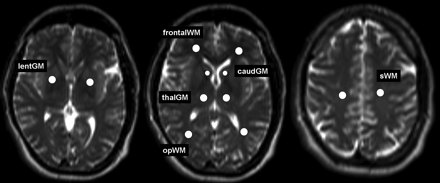

T2*, T2′, and T2 values of deep GM and WM for each hemisphere were measured in 6 ROIs chosen in different brain regions: frontal WM (frontalWM), occipitoparietal WM (opWM), subcortical WM (sWM), caudate nucleus (caudGM), thalamus (thalGM), and lentiform nucleus (lentGM) (Fig 1). For definition of the first 2 GM ROIs, the same transaxial section was used. The third ROI was located in the axial section showing the largest extent of the transaxial sectioned lentiform nucleus. The ROIs were chosen carefully to minimize partial volume effects. All ROIs were the same shape and comprised an area of 21 mm2, except for the ROI at the caudate nucleus, which was chosen with an area of 12 mm2. These 2 types of ROIs were predefined manually and then transferred for each patient intraindividually to each parameter map. No ROIs were chosen in cortical GM because of substantial partial volume effects contributed by CSF. We conducted all numeric calculations for ROI analysis using the MIPAV software. Statistical analysis was performed with SPSS 13.0 (correlation between grade of leukoaraiosis and T2, T2*, and T2′ WM values [Spearman rho]; calculation of Pearson correlation coefficients and corresponding P values for each ROI localization and the age dependence of T2*, T2′, and T2 values; and Mann-Whitney U test for comparison of T2′ values measured in patients with acute stroke with normal reference value).

Definition of 6 ROIs on T2-weighted images chosen in different brain regions: frontal WM (frontalWM), occipitoparietal WM (opWM), subcortical WM (sWM), caudate nucleus (caudGM), thalamus (thalGM), and lentiform nucleus (lentGM).